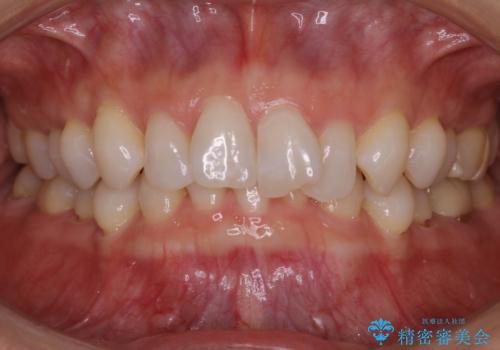

【抜歯】矯正治療とインプラントで正常な噛み合わせを実現

- 30代 女性

- マウスピース(インビザライン)

- 2年2ヶ月

- 元々は矯正治療を主訴にご来院されました。

治療を始めるにあたり、精密検査を受けていただき全体の状況を把握したうえで矯正治療の計画を立てることとなりました。

その過程で左下の6番目の歯は治療が必要な状態であることが分かり、被せ物を外して内部を確認してみると根が破折してしまっていることが判明しました。

歯が深い位置で破折している場合は基本的には抜歯が選択されます。

様々な治療プランを患者さんと相談させて頂き、最終的にインプラントで噛み合わせを回復させていくこととなり、まず悪くなっている歯を抜歯することから開始しました。